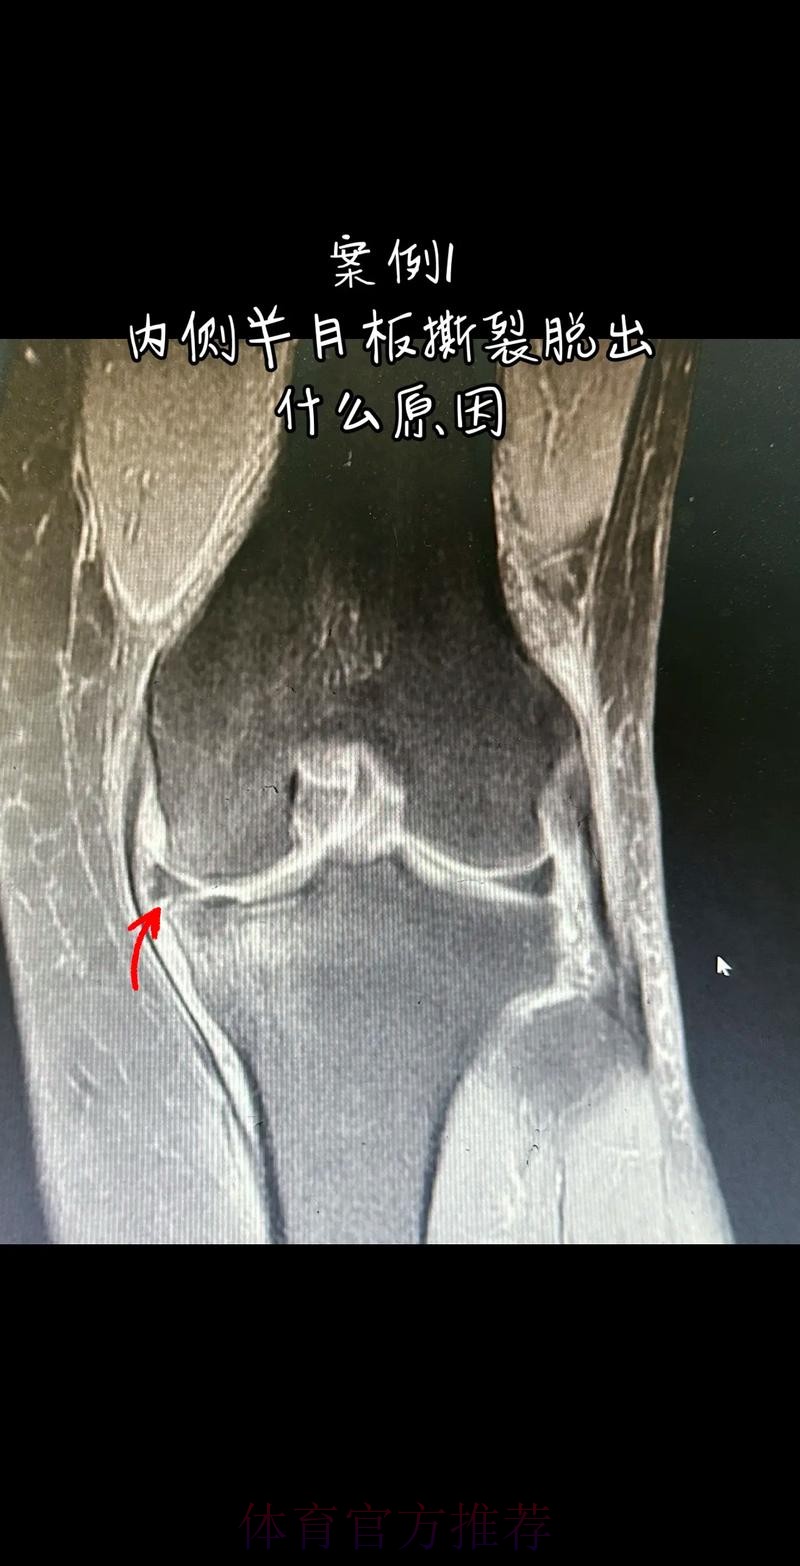

从医学角度看 半月板是膝关节内一块呈“C”形的软骨结构 其作用是缓冲冲击 稳定膝关节 并帮助分散压力 “左膝内侧半月板撕裂”通常说明在一次急停 旋转 或对抗中 半月板受到了超过其承受极限的力导致结构损伤 这类伤病常见于足球 篮球等需要频繁变向和对抗的项目 对于职业球员而言 半月板损伤严重程度不一 但共同点是都会影响支撑发力 跳跃以及变向时的稳定性 而官方给出的“预计伤缺6-8周”这个时间区间 往往对应的是中度损伤或通过微创手术加积极康复能够较快回归的情况 也意味着暂时没有出现必须长时间休战的最坏结果

表面上看 6-8周只是一个时间区间 但对顶级球队的赛程来说 这段时间可能包含多场联赛 甚至关键杯赛淘汰轮 相当于缺席一个赛季中最密集的一段周期 需要强调的是 这个“预计”并不是绝对数字 它取决于撕裂的位置 大小 修复方式 以及球员个体的恢复能力 有时若采取保守治疗 球员在6周时即可参与部分训练 但要达到比赛要求则可能接近8周甚至稍长 此外 精英运动员的康复不仅仅是伤口愈合 还包括力量恢复 协调重建 和心理自信的回归 阿拉巴要在有限时间内完成从“伤病患者”到“可靠首发”的角色转换 这一过程复杂程度远远超出一纸通告所能呈现